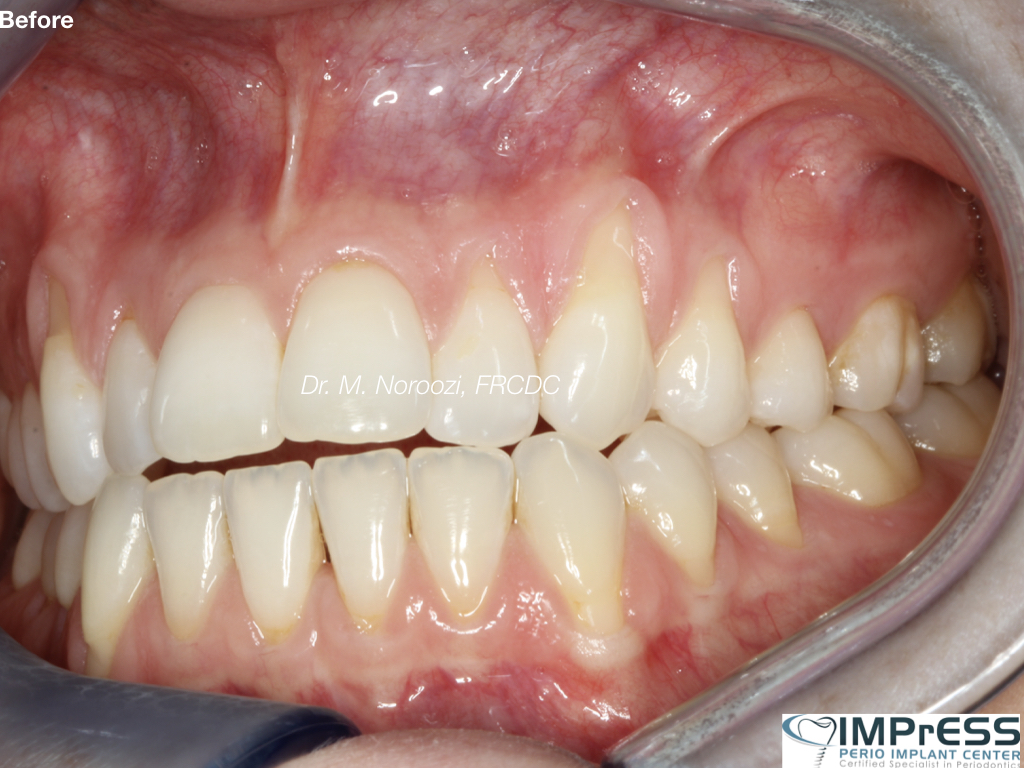

CBCT Guided Implant Surgery – Restoratively Driven Implants